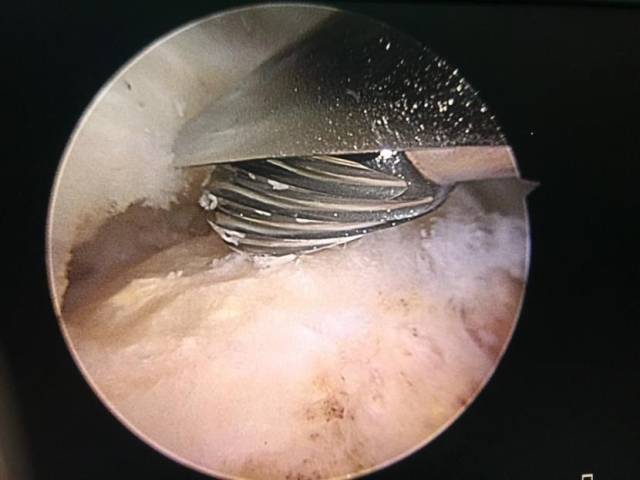

肩关节镜下检查见肱二头肌长头腱粘连严重,予以松解.

图片尺寸1920x1080